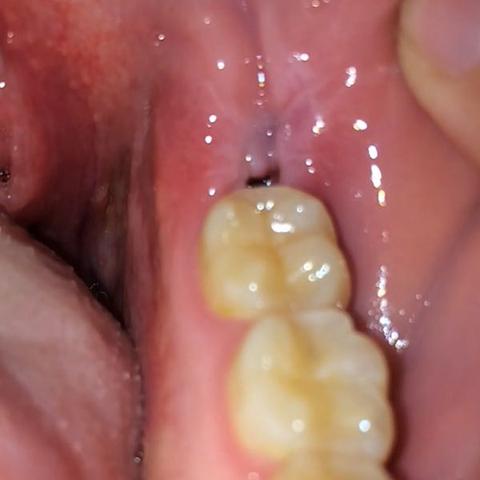

Zahnentzündung apikal bedeutet dass sich die Entzündung an der Wurzelspitze befindet. Das Anschwellen vom Zahnfleisch und evt. Wenn die Wurzel am Zahn entzündet ist macht sich dies meist bemerkbar durch die Schmerzen und ein leichtes anschwellen vom Zahnfleisch.

Dehnt sie sich bis zum Kieferknochen aus heißt. Deshalb empfindet der Betroffene keine Schmerzen obwohl sich die Entzündung mit großer Wahrscheinlichkeit schon tief in den Kiefer hinein vorgearbeitet hat. Ein traumatischer Zahnunfall oder eine Verletzung.

Entweder wurde das Zahnfleisch durch mechanische Reize verletzt oder eine Infektion mit Viren Bakterien oder Pilzen ist schuld an der Entzündung. Die Beule ist unnachgiebig aber sie ist ja noch ein Kind. Diese Bakterien können einen Abszess verursachen selbst wenn die Zähne gesund und frei von Löchern sind.

Mit der richtigen Betäubung ist die Behandlung vom Zahn ohne Schmerzen. Eine Schwellung des Zahnfleisches ist ein Anzeichen für eine Entzündung.